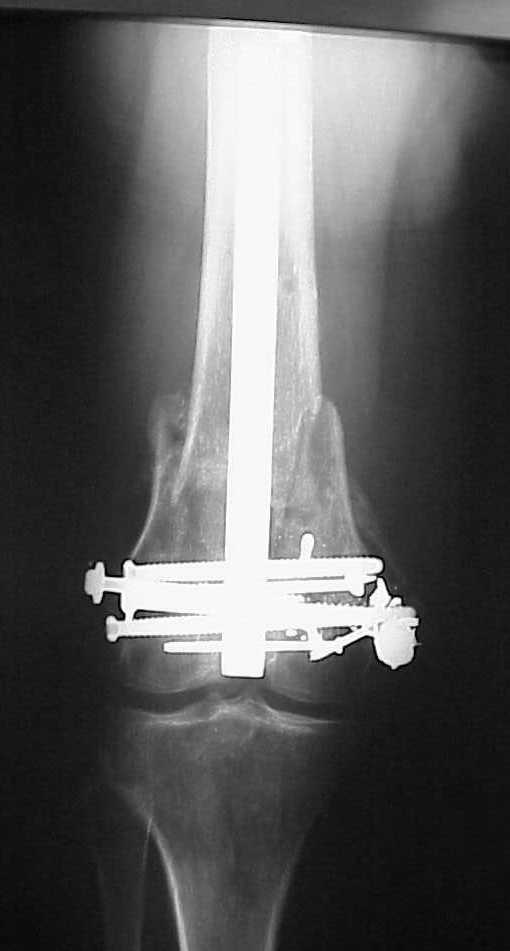

See attached case that was done several years ago before LISS. He had comminuted trochlea and anterior blocking screws were used to prevent anterior IMN cut-out.

Use 6.5 mm cannulated screws if you have and

place one anterior to where IMN will go if anterior cortex if insufficient and AP screws on either side of the IMN out of the trochlea to provide some additional varus/valgus stability. I worry about the leg going into valgus w/the lack of lateral cortex.